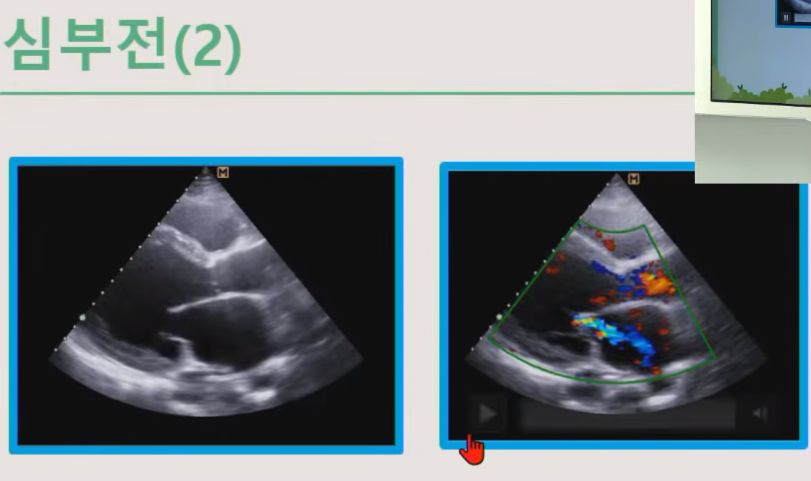

심부전

심장이 잘 못 뛰면 판막이 잘 안 닫혀서 역류가 일어난다.

ㅡ 도플러 초음파를 이용하여 혈역학적 평가 가능.